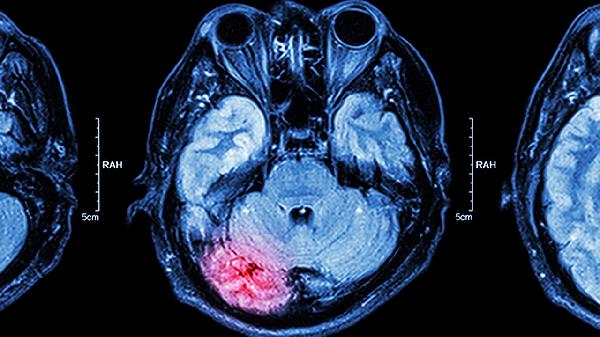

脑干肿瘤术后遗症主要有运动功能障碍、感觉异常、吞咽困难、言语障碍、平衡失调等。脑干肿瘤手术可能因肿瘤位置、手术范围等因素对周围神经组织造成影响,需结合康复治疗改善症状。